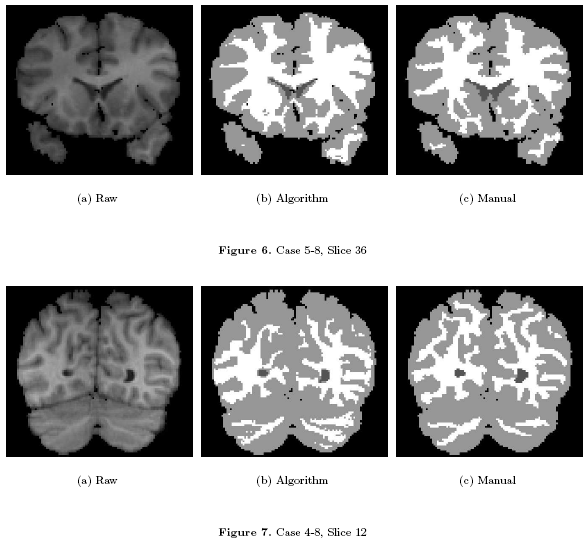

We have applied this algorithm to 20 normal brain MRI data-sets. We used publicly available data-sets from the Internet Brain Segmentation Repository (IBSR) offered by the Massachusetts General Hospital, Center for Morphometric Analysis. The IBSR data-sets are T1-weighted, 3D coronal brain scans after having been positionally normalized. Manual expert segmentations for these data-sets are publicly available and represent the ground truth used in this work.

Some Results